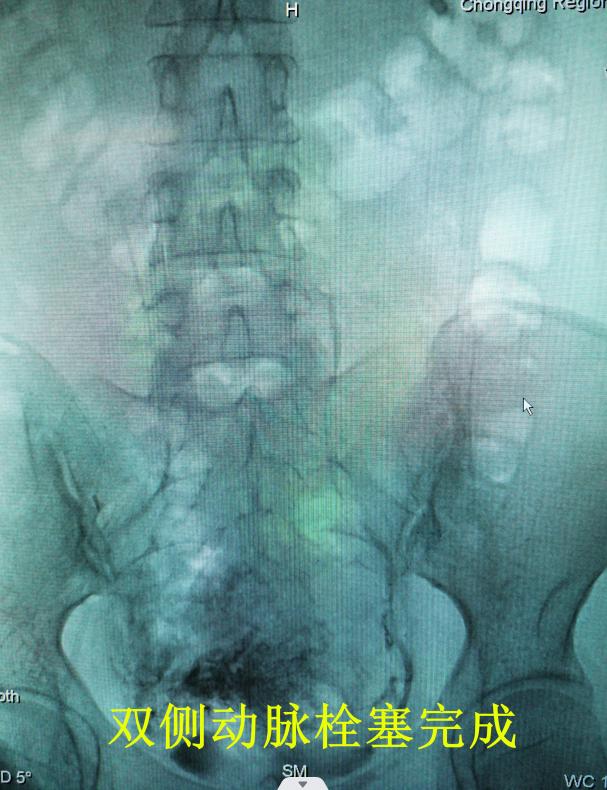

子宫动脉栓塞术是介入手术的一种,是通过股动脉置入导管,在X线指引下进入子宫动脉,用栓塞剂堵住动脉血管,避免手术时大量出血,这是一项4级手术,对医生团队和技术设备要求高。

经充分的术前讨论和准备,李春梅副主任医师带领团队首先为黎女士成功完成了“双侧子宫动脉栓塞术”,推回病房休息并观察评估,15小时后又顺利完成了“腹腔镜下剖宫产瘢痕妊娠病灶清除术+腹腔镜子宫下段修补术+子宫肌瘤剜除术+双侧输卵管结扎+肠粘连松解术+盆腔粘连松解术”6项手术及膀胱灌注。 术中出血仅50ml,生命体征平稳,返回病房,两日后康复出院。